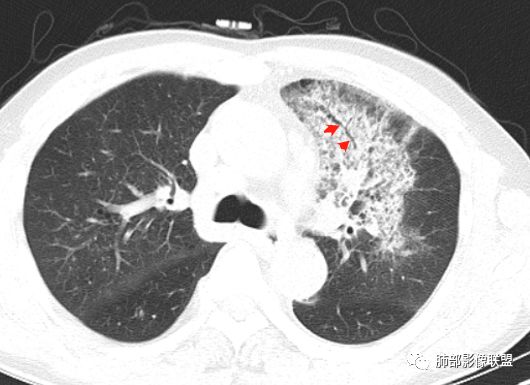

单从影像看,:右肺下叶背段结节并支气管闭塞,肿瘤可能性大;右肺底结节,强化较明显,考虑肉芽肿性病变;左肺上叶大片间质性改变,考虑感染病变;临床提示CRP增高,贫血,糖尿病,单核略高,IGE增高。一元论不好解释。

左上肺大片网格状影,内有实变,内支气管有狭窄和扩张,血管模糊,右下肺有大小多发结节,纵隔有多发淋巴结,部分钙化,还是把肿癌放前面,腺癌?

胸CT:左肺上叶前段实变,其周围及左肺上叶尖后段可见肺气肿背景下渗出性病变,病灶内可见支气管扩张,气道壁呈不规则增厚,双肺散在小结节状影;右肺下叶结节影,内可见空泡,边缘模糊,不规则。增强可见病灶内血管造影征,右肺门增大,纵隔淋巴结多发肿大。

左肺上叶大片混合网格磨玻璃影,边界清,边缘分叶膨隆,内支气管走行狭窄扩张,实变区边界清,上叶支气管管腔窄,心膈角淋巴结肿大,考虑肺炎型肺癌—腺癌。左肺下肺门结节,边缘膨隆,突入中间段及下叶支气管腔,背段支气管阻塞,周围少量小花小草,考虑鳞癌。右下叶外侧基底段结节,边缘有膨隆,有血管牵拉进入,上缘支气管贴边,考虑肺癌,性质?